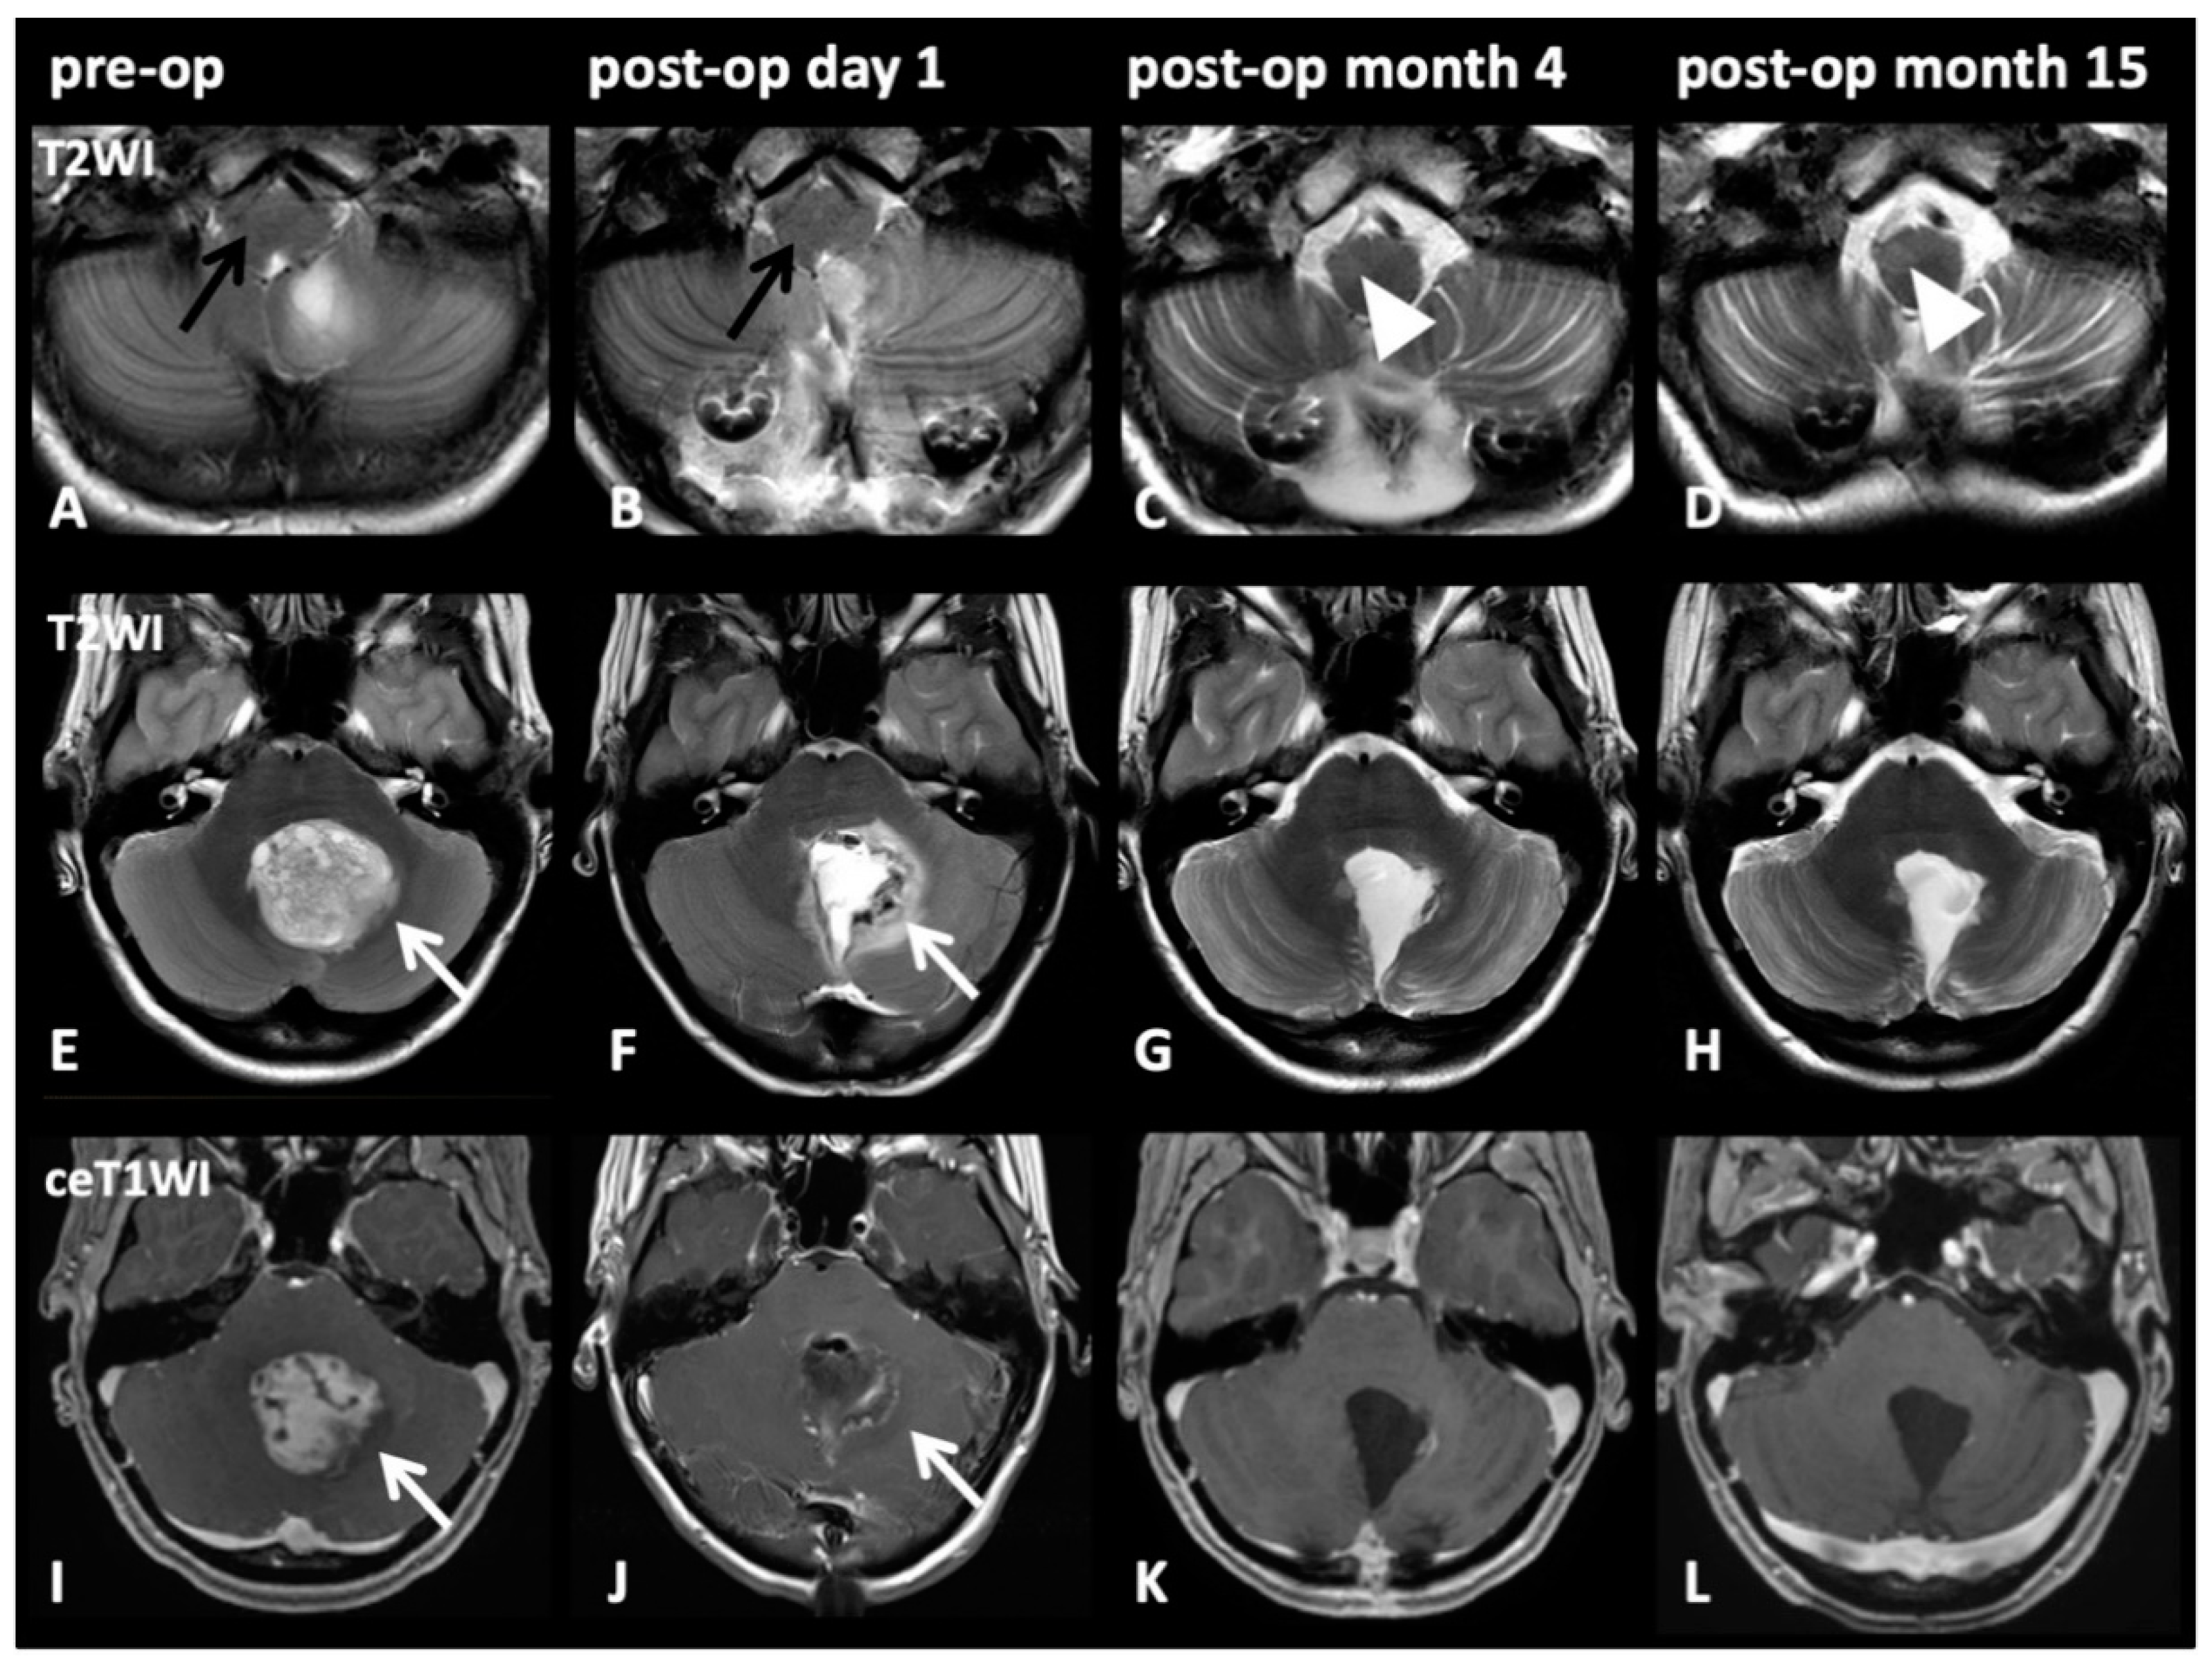

2.3. HOD-Patient Characteristics and Disease Pattern

| Pat. | Age, Sex | Diagnosis WHO° | HOD Side | Tumor Localization | Operative Approach | Lesion within GMT | Adjuvant RCT | Tumor Size (mm) [Volume] | Time Lesion to HOD | CMS |

|---|---|---|---|---|---|---|---|---|---|---|

| 1 | 20, f | pilocytic astrocytoma I° | right | 4th ventricle | paravermal trans-cerebellar | both dentate nuclei (left > right) | none | 63 × 42 × 36 [48 cm3] | 2 mo. | no |

| 2 | 60, f | pilocytic astrocytoma I° | right | 4th ventricle to vermis | paravermal trans-cerebellar | both dentate nuclei (left > right) | none | 42 × 63 × 56 [74 cm3] | 8 mo. | no |

| 3 | 32, m | pilocytic astrocytoma I° | left | 4th ventricle to vermis | paravermal trans-cerebellar | right dentate nucleus | none | 37 × 40 × 30 [22 cm3] | 6 mo. | no |

| 4 | 14, f | pilocytic astrocytoma I° | right | cerebellar vermis | paravermal trans-cerebellar | both dentate nuclei | none | 58 × 57 × 57 [94 cm3] | 4 mo. | no |

| 5 | 17, f | pilocytic astrocytoma I° | right | 4th ventricle | paravermal trans-cerebellar | left dentate nucleus | none | 33 × 34 × 39 [22 cm3] | 4 mo. | no |

| 6 | 35, m | ependymoma II° | left | 4th ventricle | midline telovelar | both dentate nuclei (right > left) | none | 42 × 15 × 20 [6 cm3] | 3 mo. | no |

| 7 | 14, m | medulloblastoma IV° | right | 4th ventricle | midline transvermian | left dentate nucleus | yes | 34 × 47 × 37 [30 cm3] | 3 mo. | no |

| 8 | 34, m | medulloblastoma IV° | bilateral | 4th ventricle | midline telovelar | both dentate nuclei | yes | 46 × 35 × 35 [28 cm3] | 10 mo. | no |

| 9 | 9, m | medulloblastoma IV° | bilateral | 4th ventricle and cerebellum | paravermal trans-cerebellar | both dentate nuclei, left SCP | yes | 53 × 37 × 48 [47 cm3] | 4 mo. | yes |

| 10 | 40, m | medulloblastoma IV° | right | 4th ventricle | paravermal trans-cerebellar and telovelar | left dentate nucleus | yes | 31 × 21 × 27 [9 cm3] | 3 mo. | no |